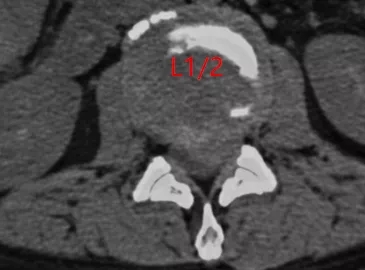

? 术前CT

入院时,患者卧床不能自理,双下肢剧烈疼痛让患者连续几个晚上睡觉都十分困难。查体显示双侧髂腰肌肌力II级,双侧股四头肌力III级,远端肌力轻度减低。鞍区感觉减退,肛门括约肌轻度松弛,小便费力。综合影像学检查结果诊断为腰1/2椎间盘脱出,马尾综合症。6月25日,在空军军医大学西京医院脊柱外科王哲主任安排下,丁坦副教授主刀实施腰1/2椎板切除减压,髓核摘除,椎间植骨融合内固定术,手术用时2小时顺利结束。